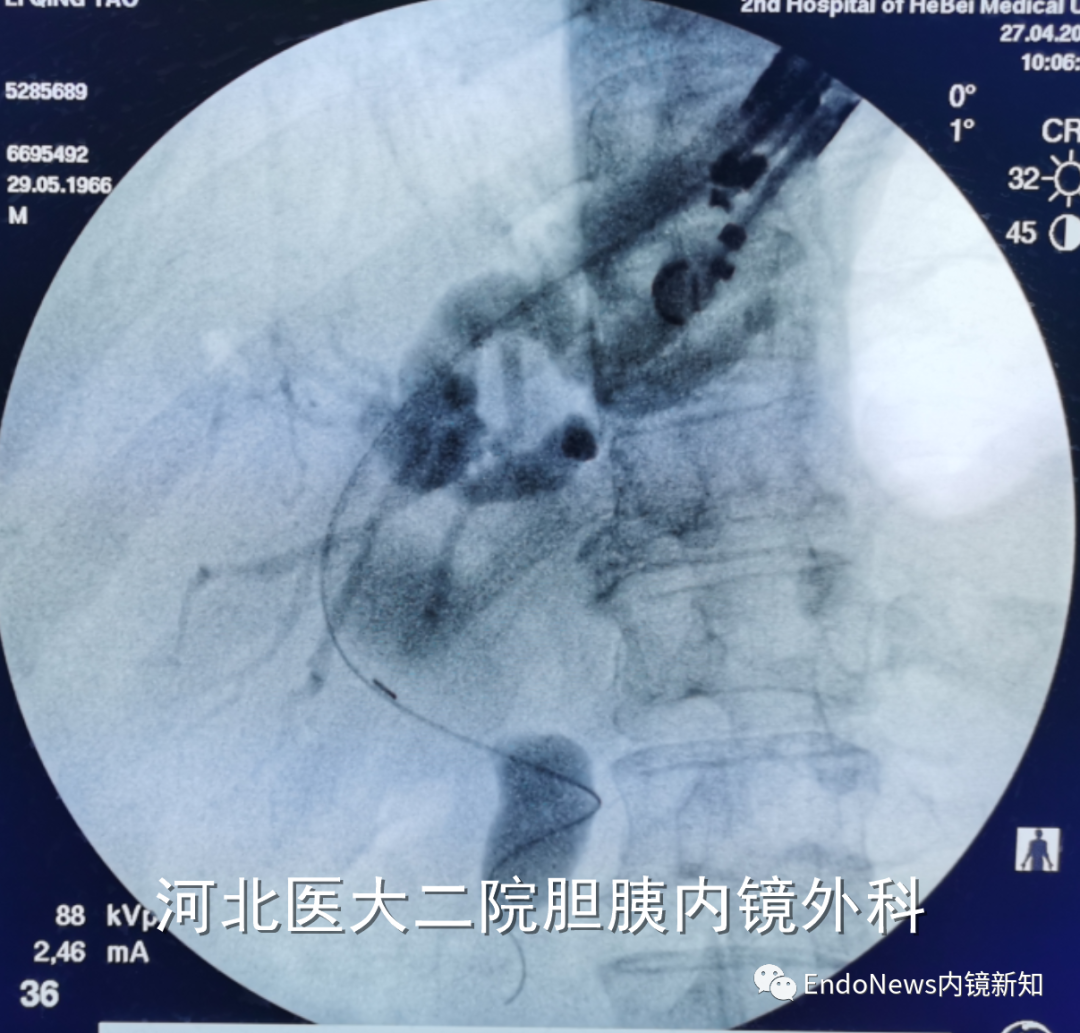

病例2:胆肠吻合口狭窄并右侧肝内胆管结石。

HGS造瘘,再碎石取石,置入双猪尾支架

在这个病例中,倘若是左肝管穿刺的第二段或第三段有结石,操作则更为困难,因此不同的病例还需要具体情况具体分析。